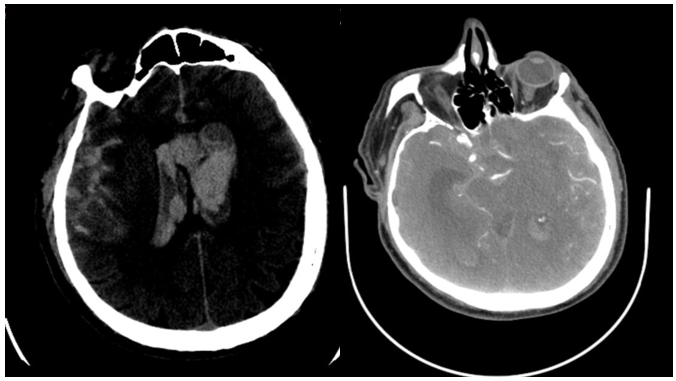

Fig 2: Brain CT-Scan of the third patient who died after few days of cerebral hemorrhage

But the third and most serious case is the one that actually motivated me to write this report because when it started, it quickly put the patient in a coma, and then after a CT scan, the problem of a brain aneurysm was confirmed, the patient never regained consciousness until they decided whether or not to perform surgery to drain the hematoma in the brain tissue or to ligate the aneurysm, because after four days in the intensive care unit, the patient died. Interestingly, this patient did not have any symptoms or complaints before the brain aneurysm ruptured and the massive bleeding that caused the patient to have this problem, and in fact, the sudden and rapid occurrence of such a problem left us all in shock and disbelief.